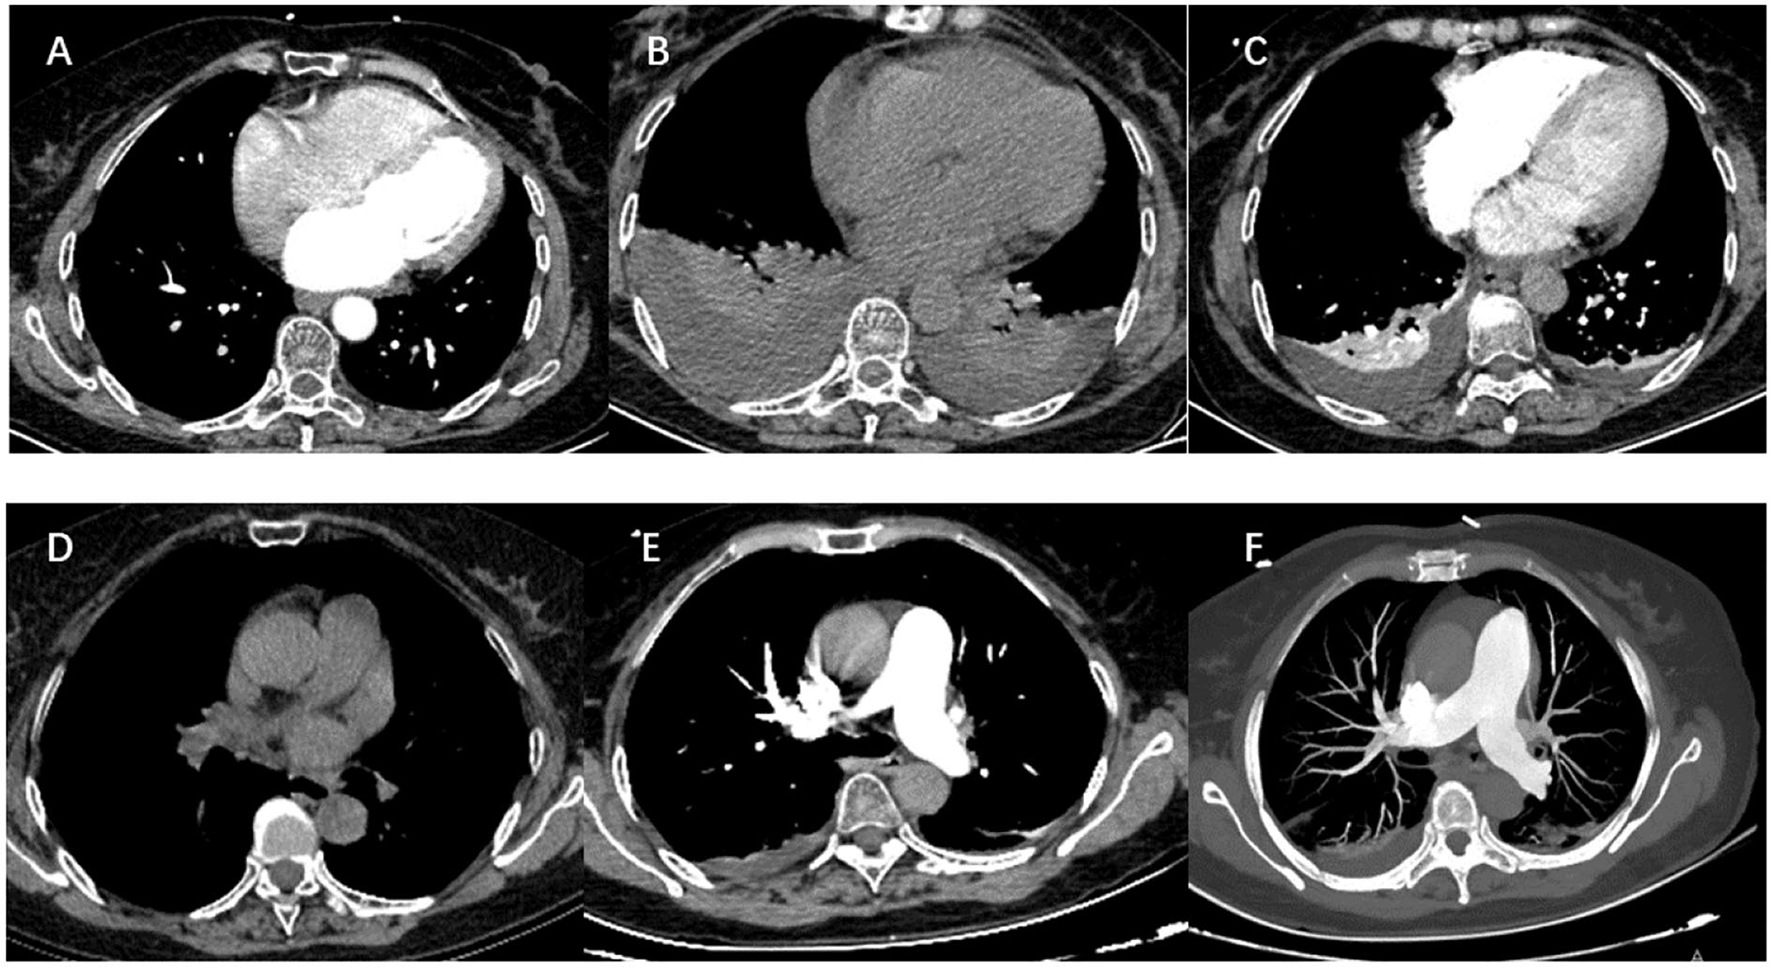

A 65-year-old woman underwent CA at our center because of increasing palpitation symptoms despite antiarrhythmic drug therapy. She had a history of hypertension, and chronic AF and had symptomatic AF confirmed by the 12-lead ECG for 1 year (Figure 3A). On admission, her routine clinical assessment and physical examination revealed irregular heart sounds, jugular venous pulsations, and hypertension. Preprocedural transesophageal echocardiography showed normal biventricular function with patent foramen ovale and no thrombus in the LA appendage. A chest computed tomography demonstrated no significant abnormalities, as shown in Figure 1A.

Figure 1

The dramatic transition of a thoracic CT scan (soft-tissue window) and pulmonary computed tomography angiography. (A) Preoperative tests: CT revealed clear lung fields bilaterally. (B) Three days after operation: CT scan showing large bilateral pleural effusions without pericardial effusion. (C) Nine days after the operation: there is a resolution of the left pleural effusion and a marked decrease in the right pleural effusion. (D) Nineteen days after operation: there is no pleural effusion on CT images. (E,F) Pulmonary computed tomography angiography ruled out pulmonary embolism.

Her health condition did not improve after treatment for 3 days. As shown in Figure 1B, massive bilateral pleural effusion alone was observed in a chest computed tomography. There was no pericardial effusion in the post-procedure TTE. Pulmonary computed tomography angiography ruled out pulmonary embolism (Figure 1). After the exclusion of infectious, metabolic, and toxic causes of pleural effusion, the criteria for PPIS were considered because our patient was found to have pleural effusions along with pleuritic chest distress and elevated levels of inflammatory markers. Then the patient was continued on glucocorticoid and antibiotic therapy. The pathological changes were resolved and the chest CT reverted to normal after 3 days of treatment, and the patient was able to be discharged out of the hospital; the chest CT is shown in Figure 1C.

At a 1-month follow-up, recovery of the patient was uneventful, and the chest CT scan displayed full expansion of the lungs with almost complete resolution of the massive pleural effusion (Figure 1D).

In this study, we present the first case of PPIS characterized as massive pleural effusion alone after RFCA of AF. In our case, a symptom cluster of chest tightness and breathlessness occurred the day after the operation. Contrast radiography suggested massive bilateral pleural effusion in the absence of pericardial effusion. Cardiac tamponade and cardiac perforation were ruled out by echocardiography. Pulmonary computed tomography angiography also ruled out pulmonary embolism (Figure 1). PPIS after the operation was considered when both elevated leukocyte count and increased C-reactive protein. RFCA is currently the most commonly used ablation technique for the treatment of AF, aiming at eliminating AF and maintaining sinus rhythm in long term. Conventional thermal radiofrequency ablation for AF is low power delivery (20–40 W) over a long duration (20–40 s). Recently, there has been increasing interest to use relatively higher power (45–70 W) over a short duration (5–10 s) (23). The goal was to achieve a high rate of transmural trauma with minimal destruction of surrounding tissues, resulting in lower rates of recurrence and higher efficiency of this solution. Compared with conventional radiofrequency ablation, a large number of studies confirmed that HPSD may create transmural lesions but lessen injurious heating of deeper structures (24–26). This particular patient was successfully treated with 60 W RFCA. The sinus rhythm of the patient recovered following the completion of pulmonary vein isolation and did not complain any discomfort, which suggested that the operation process was smooth and safe.